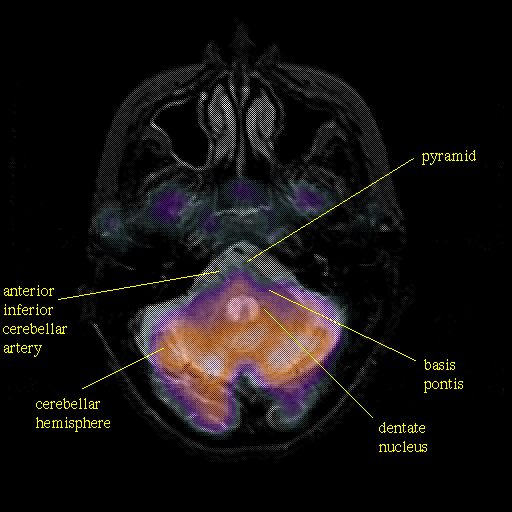

Pointers

Labeled